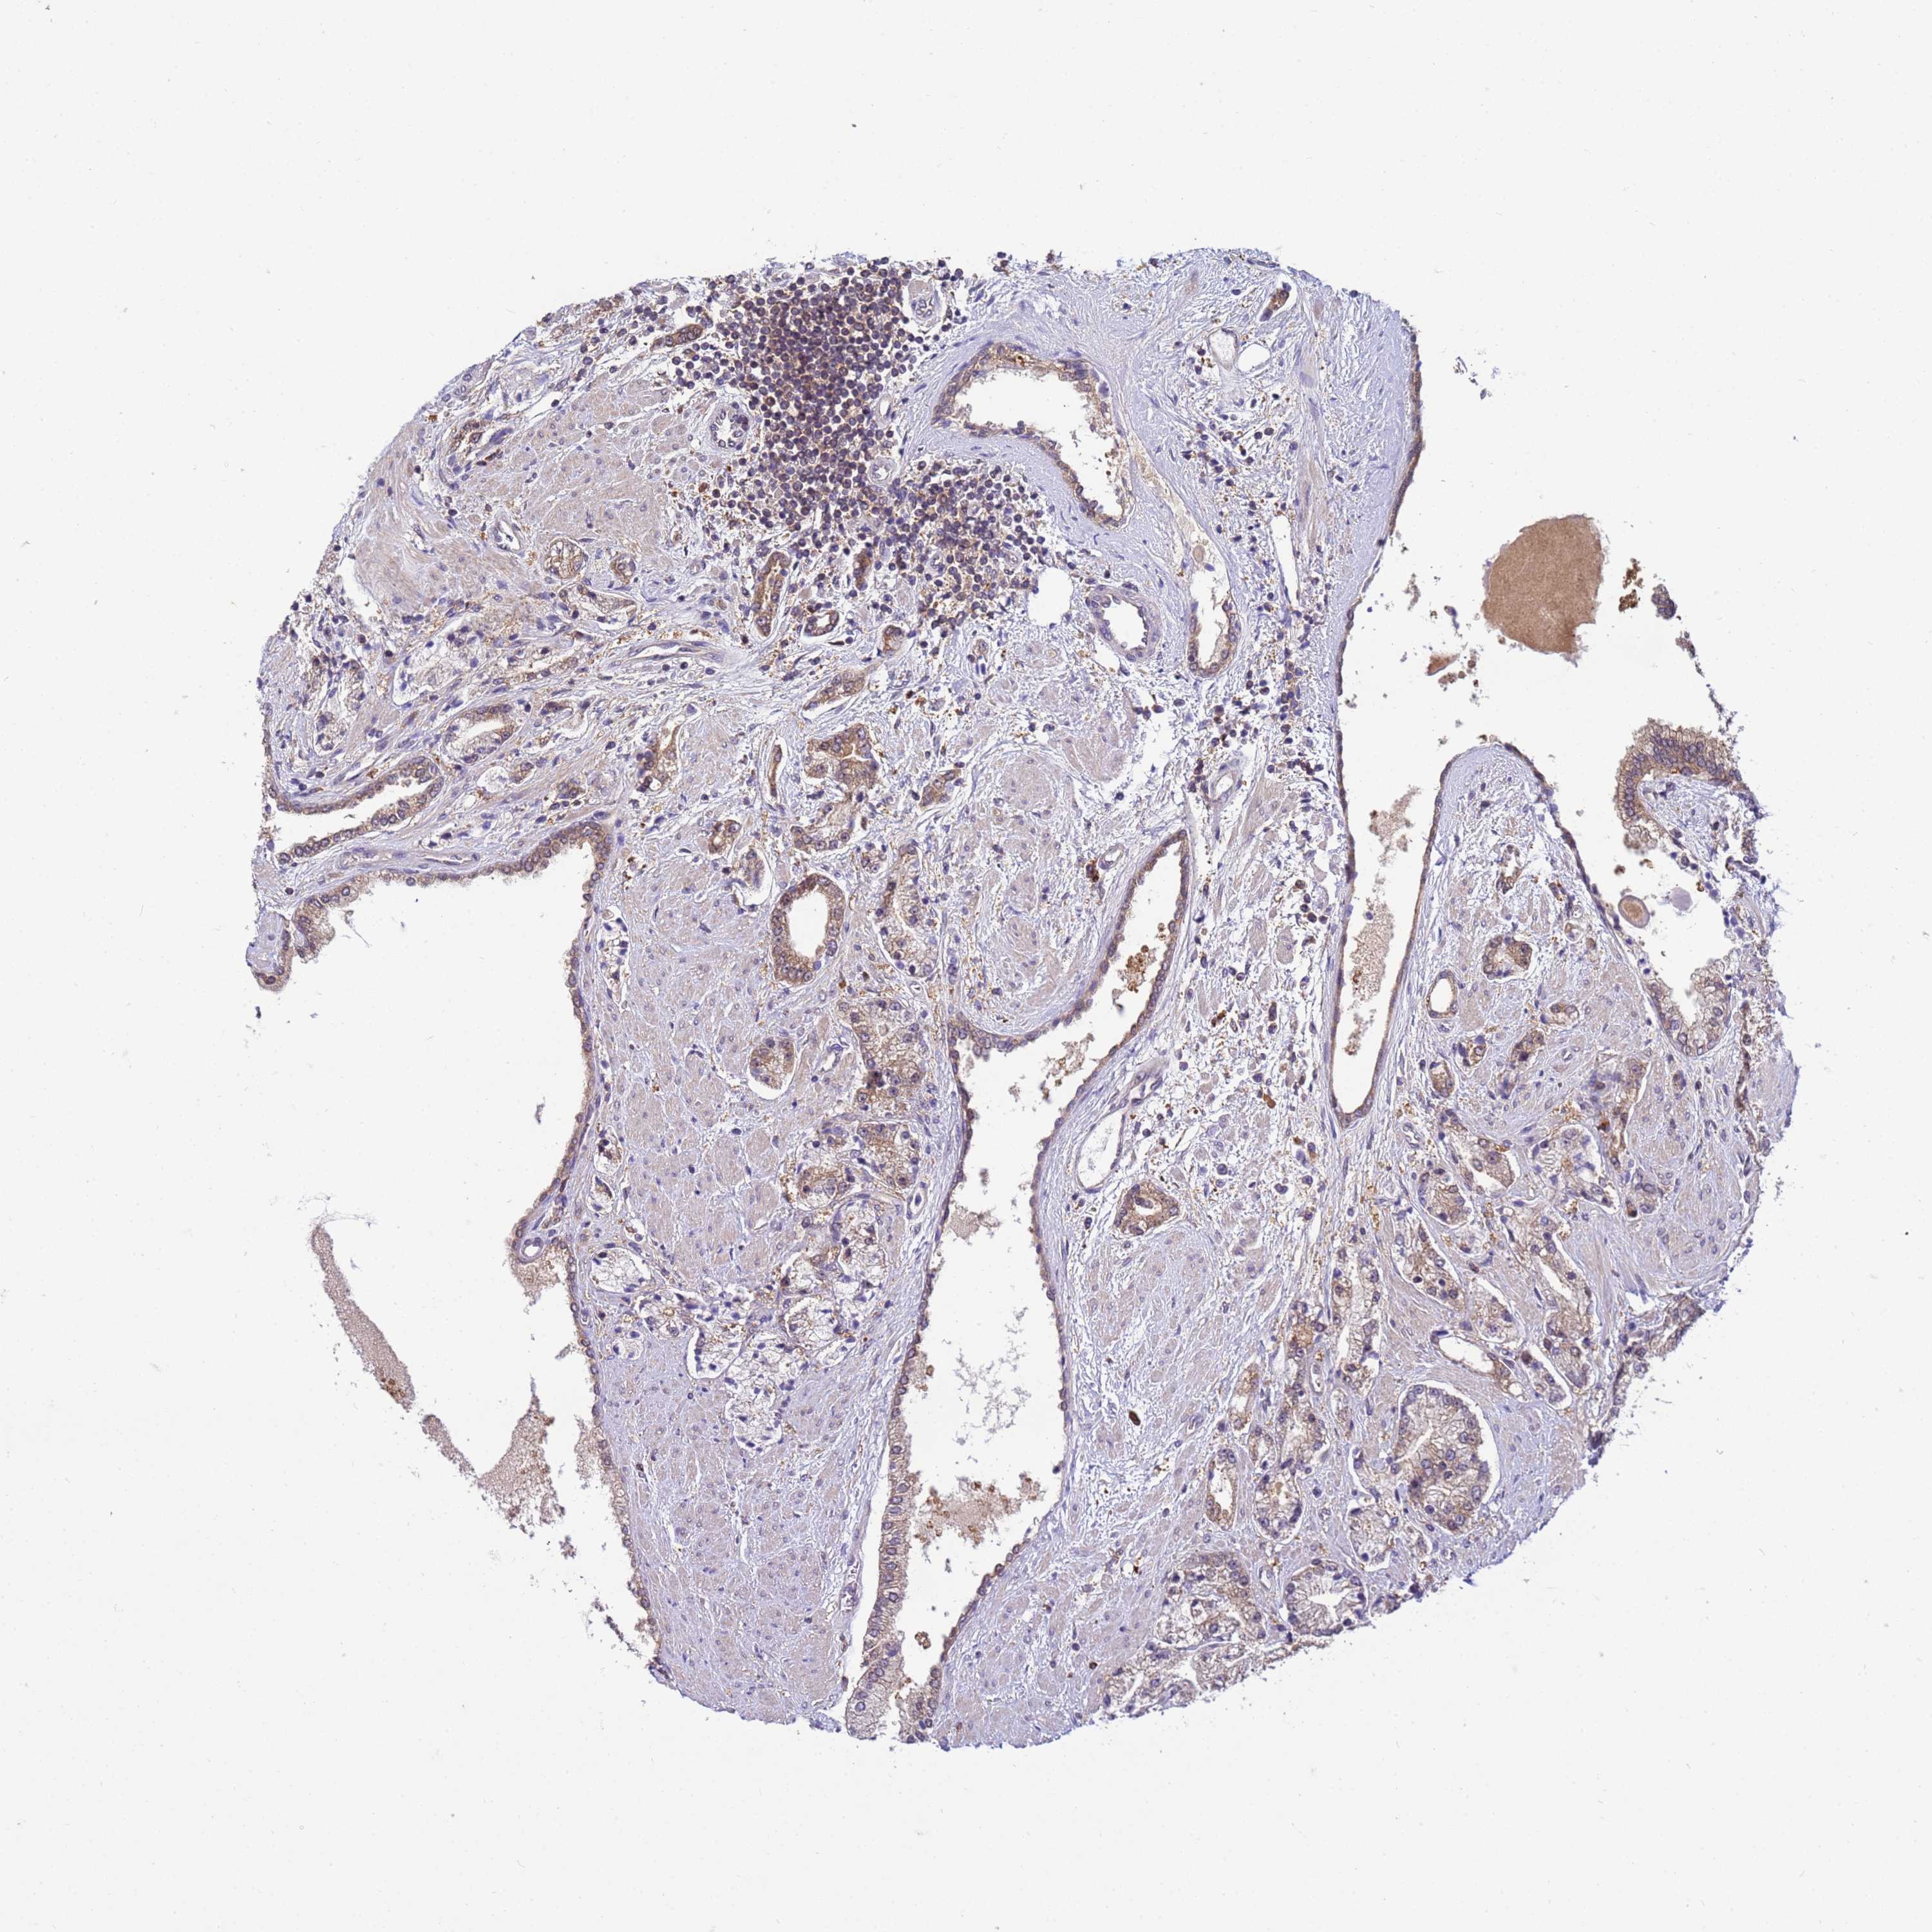

PROSTATE CANCER - Protein expressioni

A mouse-over function shows sample information and annotation data. Click on an image to view it in a full screen mode. Samples can be filtered based on level of antibody staining by selecting one or several of the following categories: high, medium, low and not detected. The assay and annotation is described here.

Note that samples used for immunohistochemistry by the Human Protein Atlas do not correspond to samples in the TCGA dataset.

Antibody stainingi

Antibody staining in the annotated cell types in the current human tissue is reported as not detected, low, medium, or high, based on conventional immunohistochemistry profiling in selected tissues. This score is based on the combination of the staining intensity and fraction of stained cells.

Each image is clickable and will lead to virtual microscopy that enables deeper exploration of all samples and also displays staining intensity scores, fraction scores and subcellular localization as well as patient and tissue information for each sample.

Antibody HPA021453

Antibody HPA045649

Staining

High

Medium

Low

Not detected

Intensity

Strong

Moderate

Weak

Negative

Quantity

>75%

75%-25%

<25%

None

Location

Nuclear

Cytoplasmic/membranous

Cytoplasmic/membranous,nuclear

Adenocarcinoma, NOS

Adenocarcinoma, High grade

Adenocarcinoma, Low grade